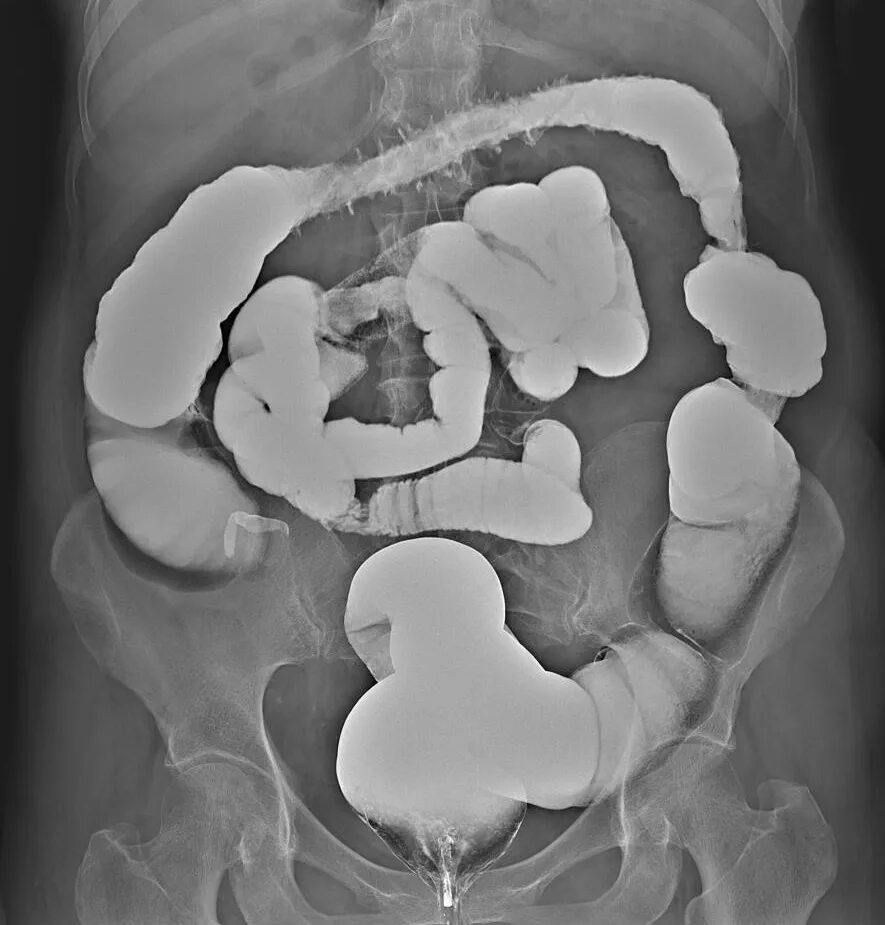

Ирригоскопия с двойным контрастированием